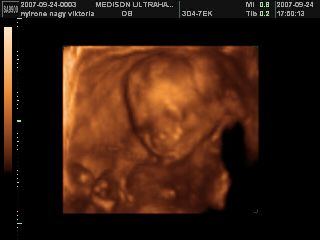

Na megjöttünk az uh-ról, 17 órára volt időpontunk, de majd fél órát csúszott a dolog, mert a doki később tudott bejönni! Minden rendben van, mindene magvan, annyi, amennyinek lennie kell, normál a szíve, a vesék rendben, gyomortelítődés van, méhlepény a fundusban, köldökzsinór 3 erű, viszont nem igen látszott, hogy milyen nemű! A doki szerint inkább lány, mint fiú, de egyáltalán nem mondta egyértelműre, és nem is látszott, összeszorította a lábacskáit a kis szégyenlős! :lol: De a lényeg az, hogy egészséges, és végre láttam az arcát is! :D